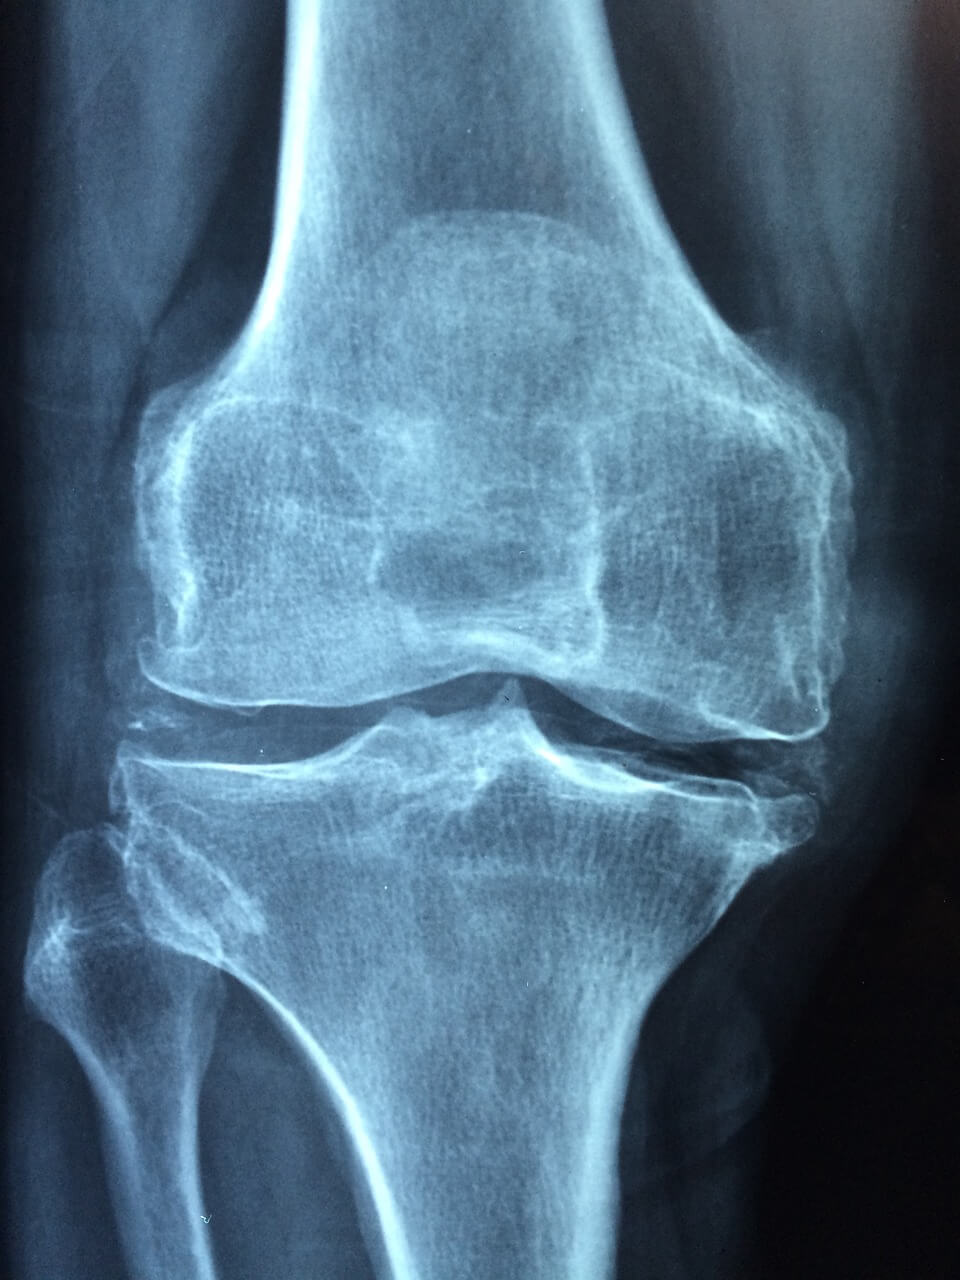

여성이 골다공증의 고도의 위협을 받는 이유 뼈가 약하고 약화되는 것을 특징으로 하는 질환인 골다공증은 특히 증가하는 인구에게 심각한 건강 문제를 보여줍니다. 골다공증은 남성과 여성 모두에게 영향을 미치지만, 그 빈도와 융통성에는 눈에 띄는 성별 차이가 있습니다. 여성은 남성에 비해 주로 고도의 위협과 함께 골다공증의 영향을 불균형적으로 받습니다. 이런 성별 차이는 자연적, 호르몬적, 그리고 생명적 요인의 조합에서 비롯됩니다. 여성의 골다공증 취약성 증가의 주요 원인 중 하나는 뼈 점도를 유지하는 데 중추적인 호르몬인 에스트로겐의 영향입니다. 그리고 에스트로겐은 골 대사를 조절하는 데 중요한 역할을 하며, 조골 세포라고 하는 뼈를 형성하는 세포의 활동을 억제합니다. 여전히 폐경기 동안 여성은 에스트로겐 상황이 크게 감소하여 뼈 손실이 가속화되고 골다공증에 대한 취약성이 증가합니다. 마찬가지로, 여성은 남성에 비해 뼈가 낮고 가벼운 경향이 있어 뼈 강도에 관해서는 구조적으로 불리합니다. 또한, 여성은 일반적으로 남성보다 더 긴 날짜를 가지고 있는데, 이는 골다공증과 관련된 나이와 관련된 뼈 손실에 더 오랜 기간 동안 노출된다는 것을 의미합니다. 골다공증의 성별 차이에 기여하는 다른 요인으로는 뼈 수치, 근육량, 그리고 생명 행동의 차이가 있습니다. 예를 들어, 여성은 뼈 건강에 필수적인 칼슘과 비타민 D가 부족한 운동과 식단에 참여할 가능성이 더 높습니다. 또한, 코르티코스테로이드와 일부 유형의 항우울제와 유사한 여성에게 일반적으로 특정된 특정 세부 사항은 뼈 손실과 골절의 위협을 증가시킬 수 있습니다. 골다공증의 결과는 심오하고 파괴적인 골절, 이동성 저하, 습관적인 고통, 그리고 삶의 질 저하로 이어질 수 있습니다. 골다공증이 여성에게 미치는 불균형한 부담을 고려할 때, 삼림 벌채, 조기 발견 및 그들의 특정 요구 사항에 맞는 수술을 위한 전략을 우선시하는 것이 필수적입니다. 그리고 여성의 뼈 건강과 골절 삼림 벌채를 촉진하기 위한 교육 및 마음 챙김 기업은 매우 중요합니다. 정기적인 체중 감량 운동을 장려하고, 칼슘 및 비타민 D 입력을 최적화하고, 흡연과 과도한 알코올 섭취를 피하며, 의료 제공자와 함께 세부 사항의 암묵적인 함정과 이점을 선동하는 것은 골다공증의 영향을 완화하는 데 필수적인 방법입니다. 또한 의료 프로그램과 지침은 개별 테스트, 치료 및 지원 서비스에 대한 무관심한 접근을 통해 골다공증의 성별 차이를 해결해야 합니다.

만약 상태의 심각성을 무시하고 방치한다면, 뼈 골절을 훨씬 넘어 확장되는 심각한 합병증으로 이어질 수 있습니다. 뼈가 약해지면서 골절의 위협이 특히 턱, 엉덩이, 손목에서 기하급수적으로 증가합니다. 이러한 골절은 급성 통증과 장애뿐만 아니라 삶의 질에도 상당한 영향을 미칩니다. 또한, 비착용 골다공증은 습관적인 통증, 독립성 상실, 이동성 저하 등에 영향을 미쳐 사회적 절연과 우울증으로 이어질 수 있습니다. 또한, 골다공증과 관련된 골절은 척추 흉터로 인한 폐활량 감소와 사망 위협 증가와 유사한 장기적인 결과를 초래할 수 있습니다. 이러한 괴로운 합병증을 완화하고 전반적인 건강과 웰빙을 구하기 위한 예방 조치와 적용 가능한 치료법으로 골다공증을 조기에 해결하는 것이 가장 중요합니다. 흔히 "조용한 불만"으로 언급되는 골다공증은 뼈 점도가 점진적으로 감소하여 뼈가 골절에 더 취약해지는 것이 특징입니다. 골다공증은 남녀 모두에게 영향을 미치지만, 특히 폐경 후 여성은 호르몬 변화 및 기타 요인으로 인해 상당히 진행된 위협에 있습니다. 미리 신경 쓰지 않으면 골다공증은 신체 건강뿐만 아니라 내부 및 사회 복지에 영향을 미치는 합병증의 큰 문제로 이어질 수 있습니다. 골다공증의 가장 즉각적이고 명백한 합병증은 뼈 골절입니다. 골절은 일반적으로 턱, 엉덩이, 손목과 유사한 체중을 견디는 뼈에서 발생합니다. 특히 척추 골절은 척추 골절(척추)과 유사한 심각한 역통, 키 손실, 척추 흉터를 얻을 수 있으며, 이는 장애인 이동성 장애와 폐활량 감소로 이어질 수 있습니다. 종종 계단식으로 나빠지는 고관절 골절은 특히 노인 성인 사이에서 장애, 독립성 상실, 사망 위협 증가를 포함하여 치명적인 결과를 초래할 수 있습니다. 손목 골절은 또한 손 기능과 양보 주행 조건을 자극할 수 있습니다. 골절로 인한 신체적 고통과 장애를 넘어, 옷을 입지 않은 골다공증은 내부 건강과 삶의 질에 깊은 역고발을 할 수 있습니다. 골절로 인한 습관적인 고통은 우울증, 불안, 전반적인 건강 저하로 이어질 수 있습니다. 골절로 인한 독립성과 이동성의 상실은 장기간의 관리와 지원을 받아 절연에 대한 열정과 타인에 대한 의존으로 이어질 수 있습니다. 마찬가지로, 골다공증과 관련된 골절도 건강에 전신적인 영향을 미칠 수 있습니다. 또한, 척추 골절로 인한 척추 흉터와 폐활량 감소는 호흡기 기능을 약화시키고 호흡기 감염과 합병증의 위협을 증가시킬 수 있습니다.